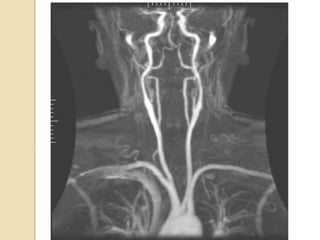

Carotid orVertebral artery dissection

 Catheter angiography has been traditionally used for

diagnosis of carotid dissection.

 MRI +fat saturation along with 3D TOF MRA characterise

dissecting hematoma, associated pseudo-aneurysm & length

and caliber of residual patent lumen.

 MRI with MRA is currently the investigation of choice for

suspected dissection.

 Not nearly as helpful in vertebral artery dissections